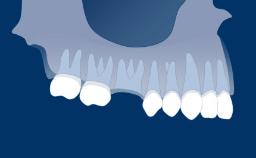

There are many conventional fixed treatment options that can be considered for the replacement of missing teeth. They include Fixed Dental Prostheses or FDPs, fixed cantilever FDPs and resin-bonded FDPs.

This module will discuss the advantages and disadvantages of conventional fixed treatment options for replacing missing teeth and compare their published treatment outcomes and indications with those of implant-supported prostheses.